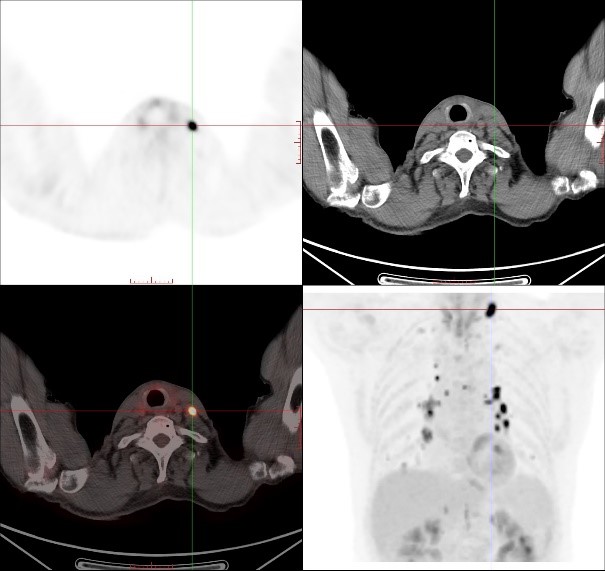

因此,临床医生给患者进行了传统的颈胸部增强CT检查以了解术后颈部情况,并试图寻找可能存在的原发病灶,但令人遗憾的是,增强CT并没有发现原发灶及转移相关证据。于是,医生决定给患者做一个全身PET/CT检查。

对于贺老伯来讲,超声及颈胸部增强CT检查均未能发现颈部、纵隔及肺门异常淋巴结,而PET/CT准确地找到这些异常淋巴结,就像多盏灯将这些隐藏的可疑淋巴结点亮一样,让可疑病灶无处遁形,为临床确定精准治疗方案提供帮助。